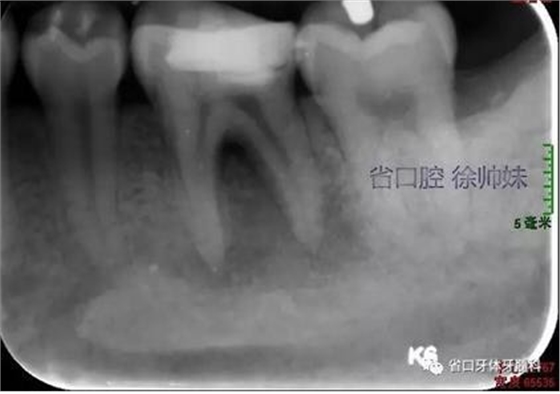

根尖片(圖2)示36大面積充填物近髓,根尖周及根分叉大面積低密度影。

圖2 術(shù)前根尖片